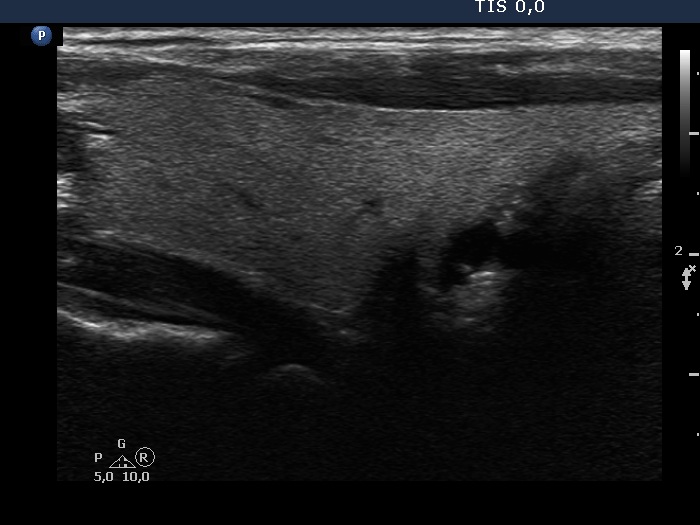

The shape of the nodule - case 1370 (ultrasonographic picture 2)

Right lobe, longitudinal scan.